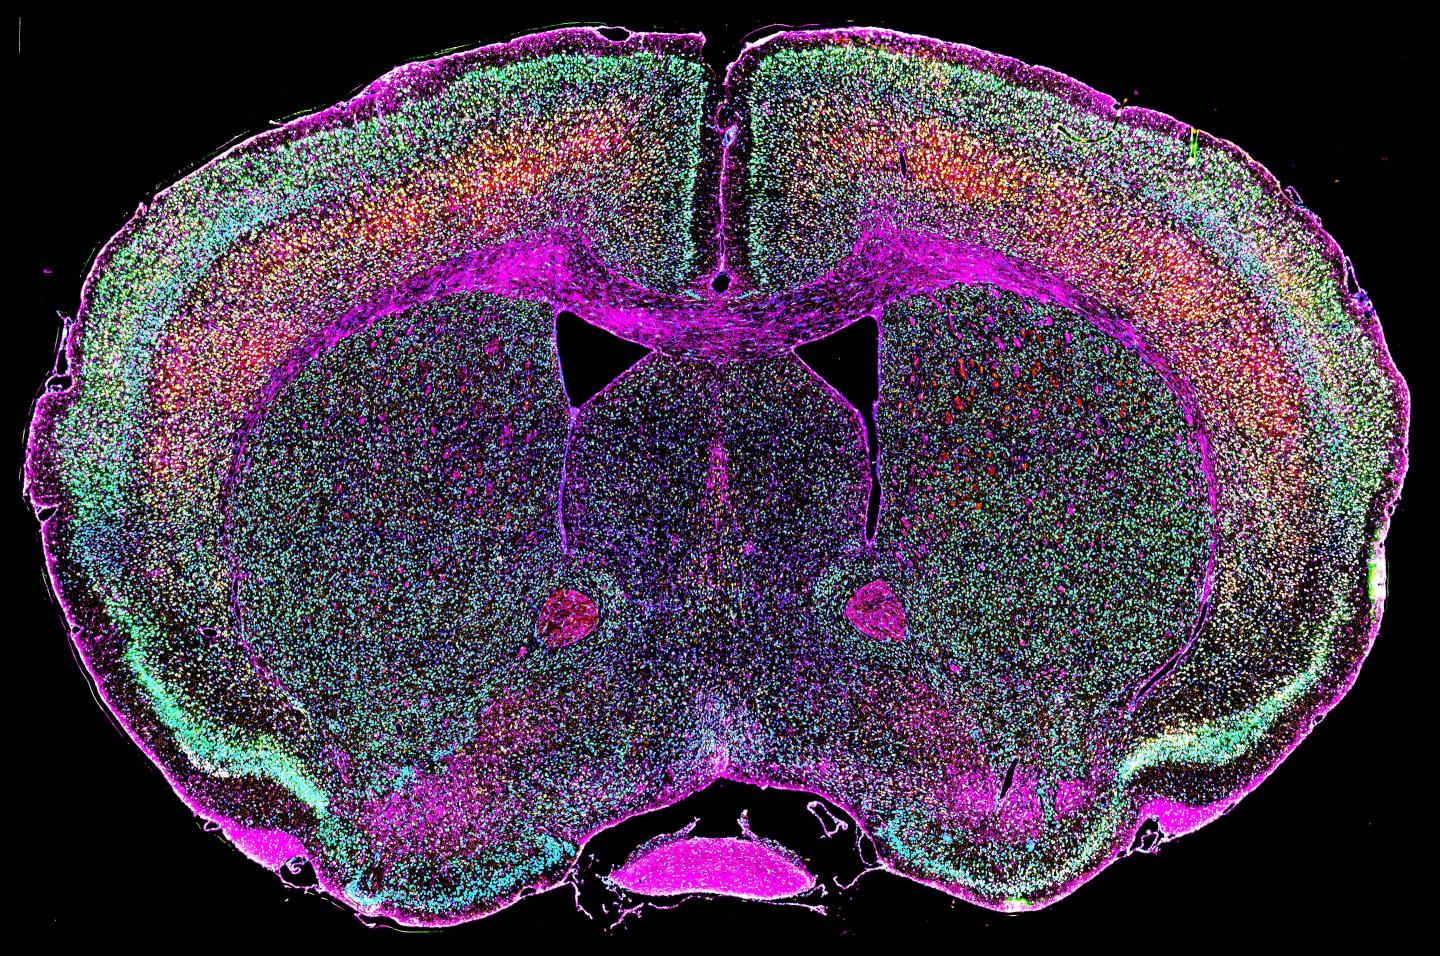

To test the role of HERVs in ALS, the scientists genetically modified mice so that their neurons activated the HERV-K env gene. The mice died earlier than normal and had problems with balance and walking that progressively worsened with age. When the scientists inspected the brains, spinal cords and muscles of these mice they found that only motor neurons, the cells that control movements and die in ALS, were damaged. Cells in other parts of the nervous system remained healthy.